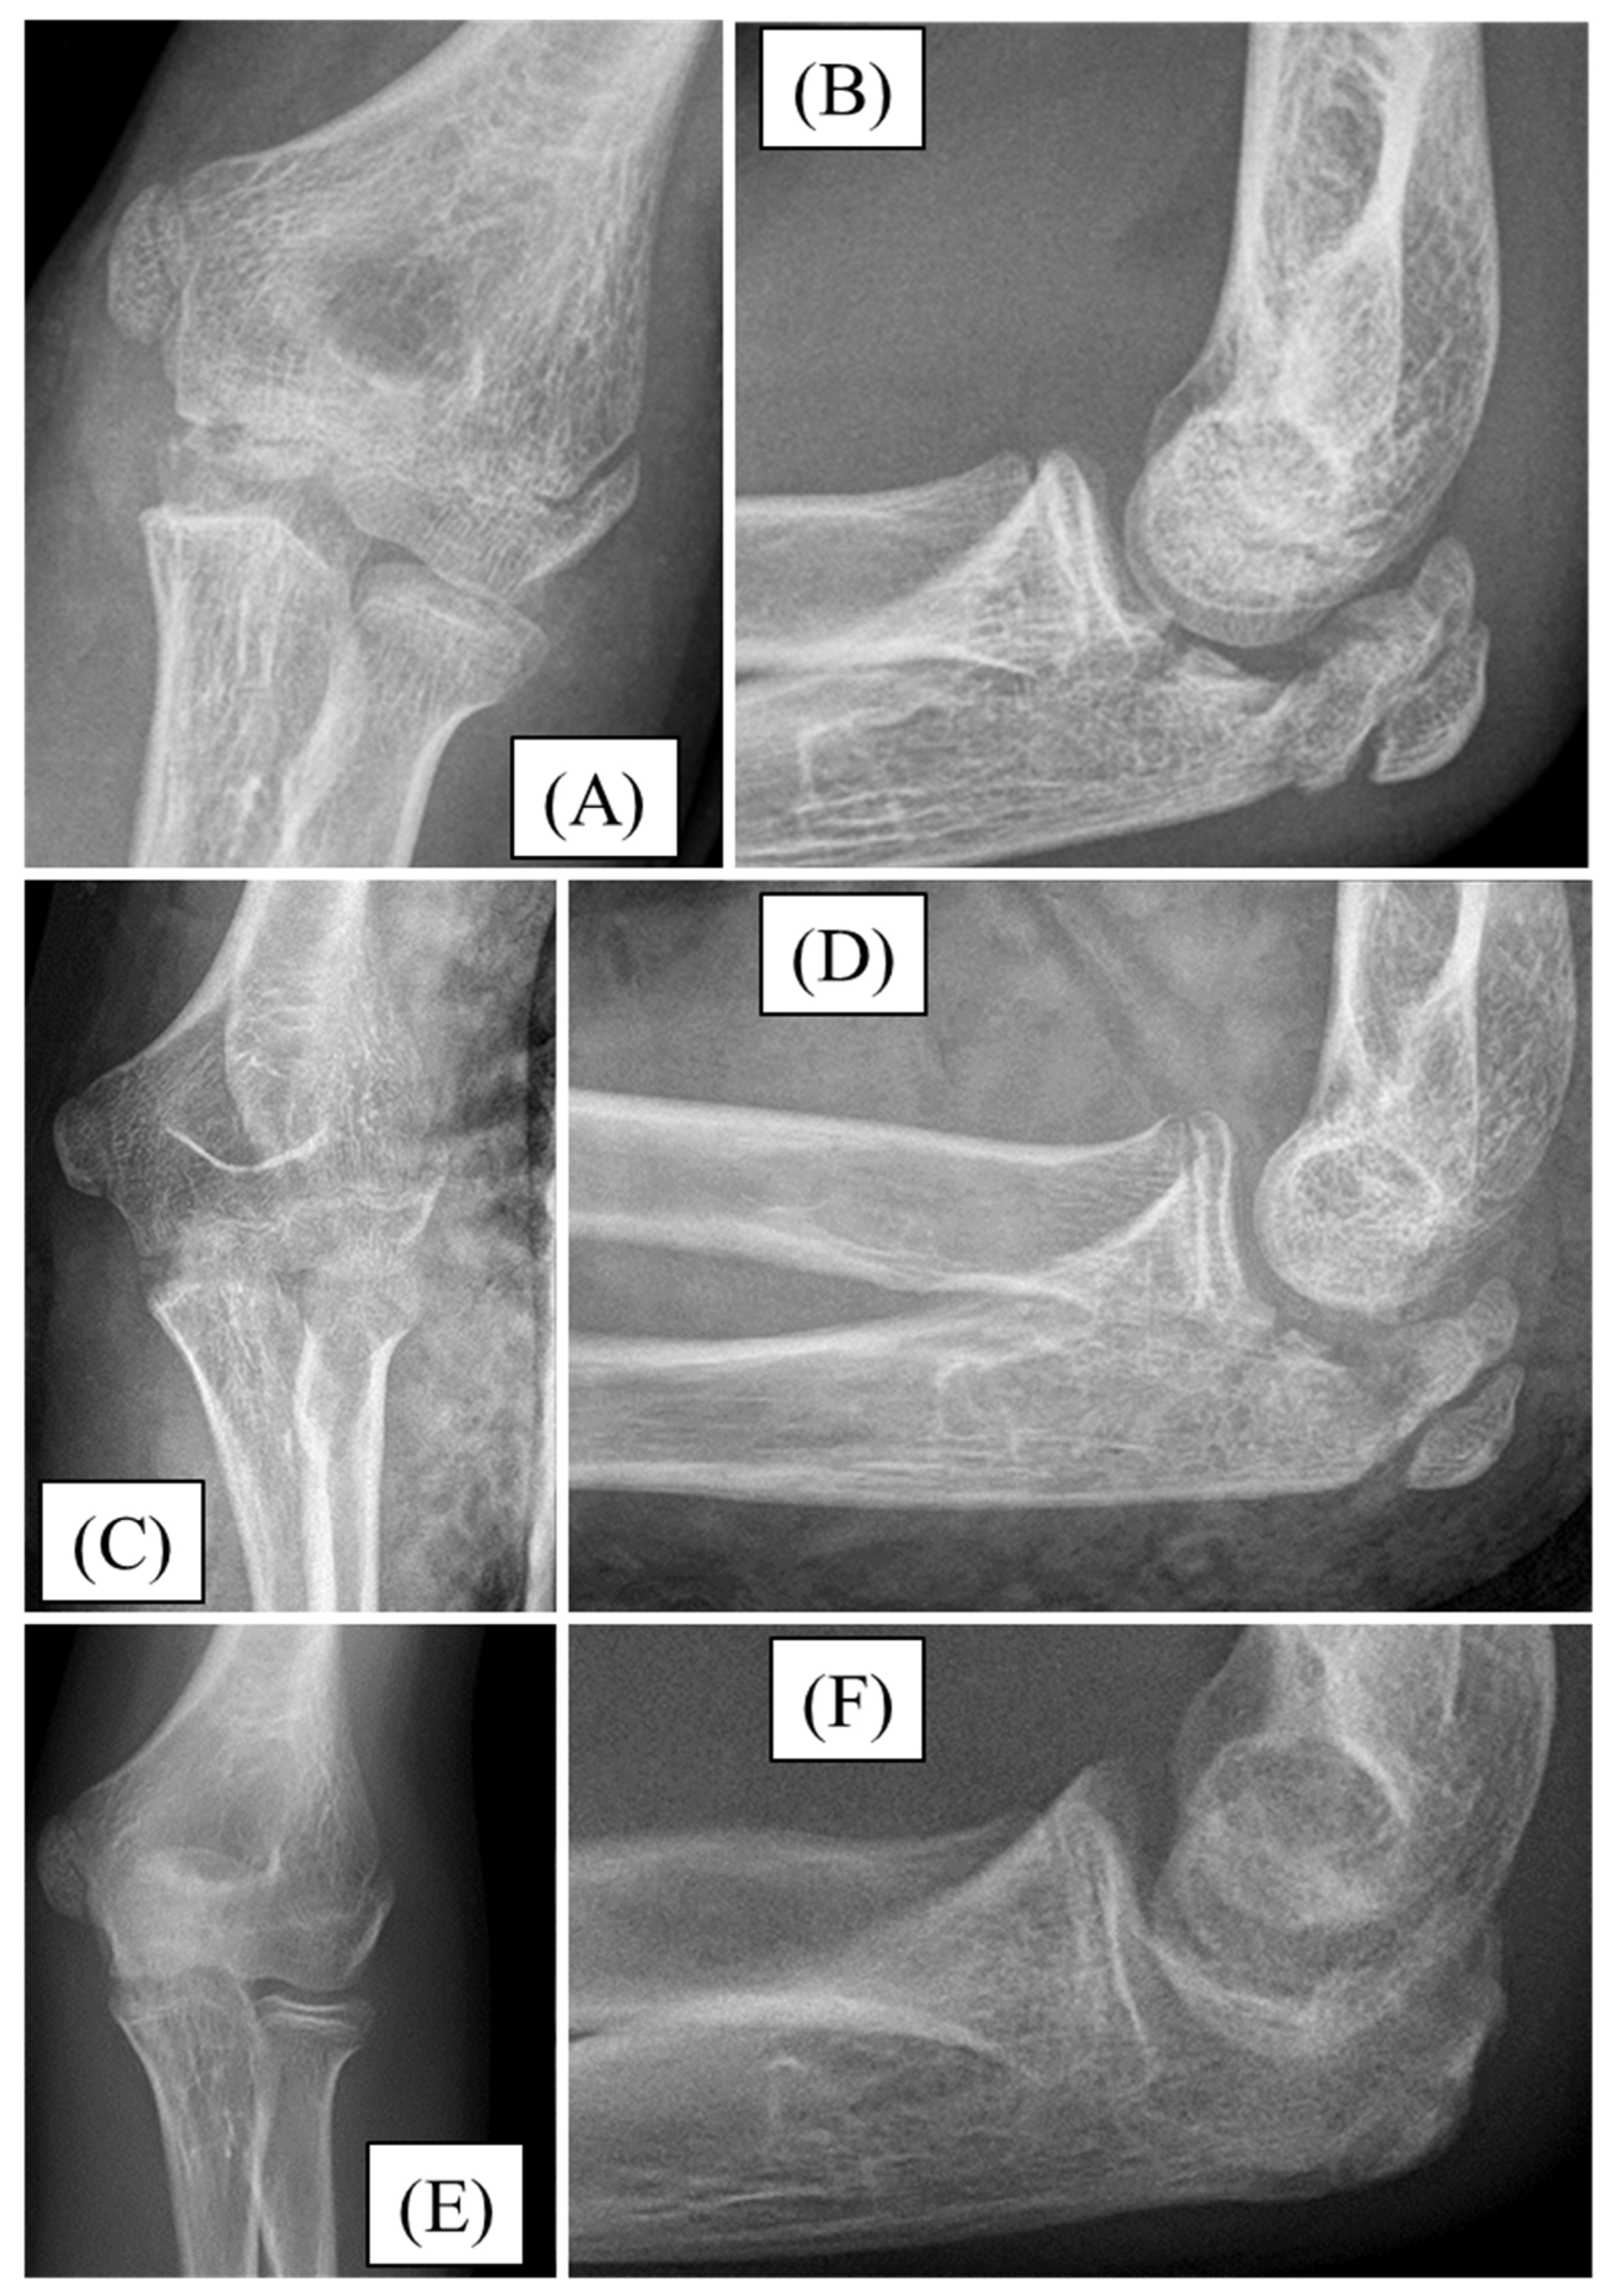

3.2. Case 2

3.3. Case 3